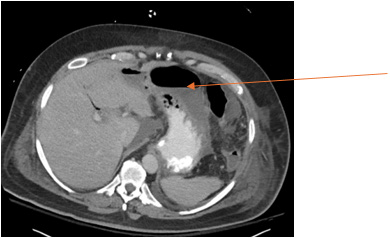

He then underwent an uneventful pancreaticoduodenectomy (Whipple) procedure, with negative margins. On POD 5, he developed a leukocytosis. A CTAP was performed and demonstrated ileus, pockets of fluid, and pneumoperitoneum, indicating possible abscess formation (Image 2). A pigtail drain was placed in this abscess by IR on the same day, and TPN was initiated. Drain fluid was analyzed and consistent with a bile leak and polymicrobial infection. On POD 12, enteral nutrition was initiated through a GJ tube.